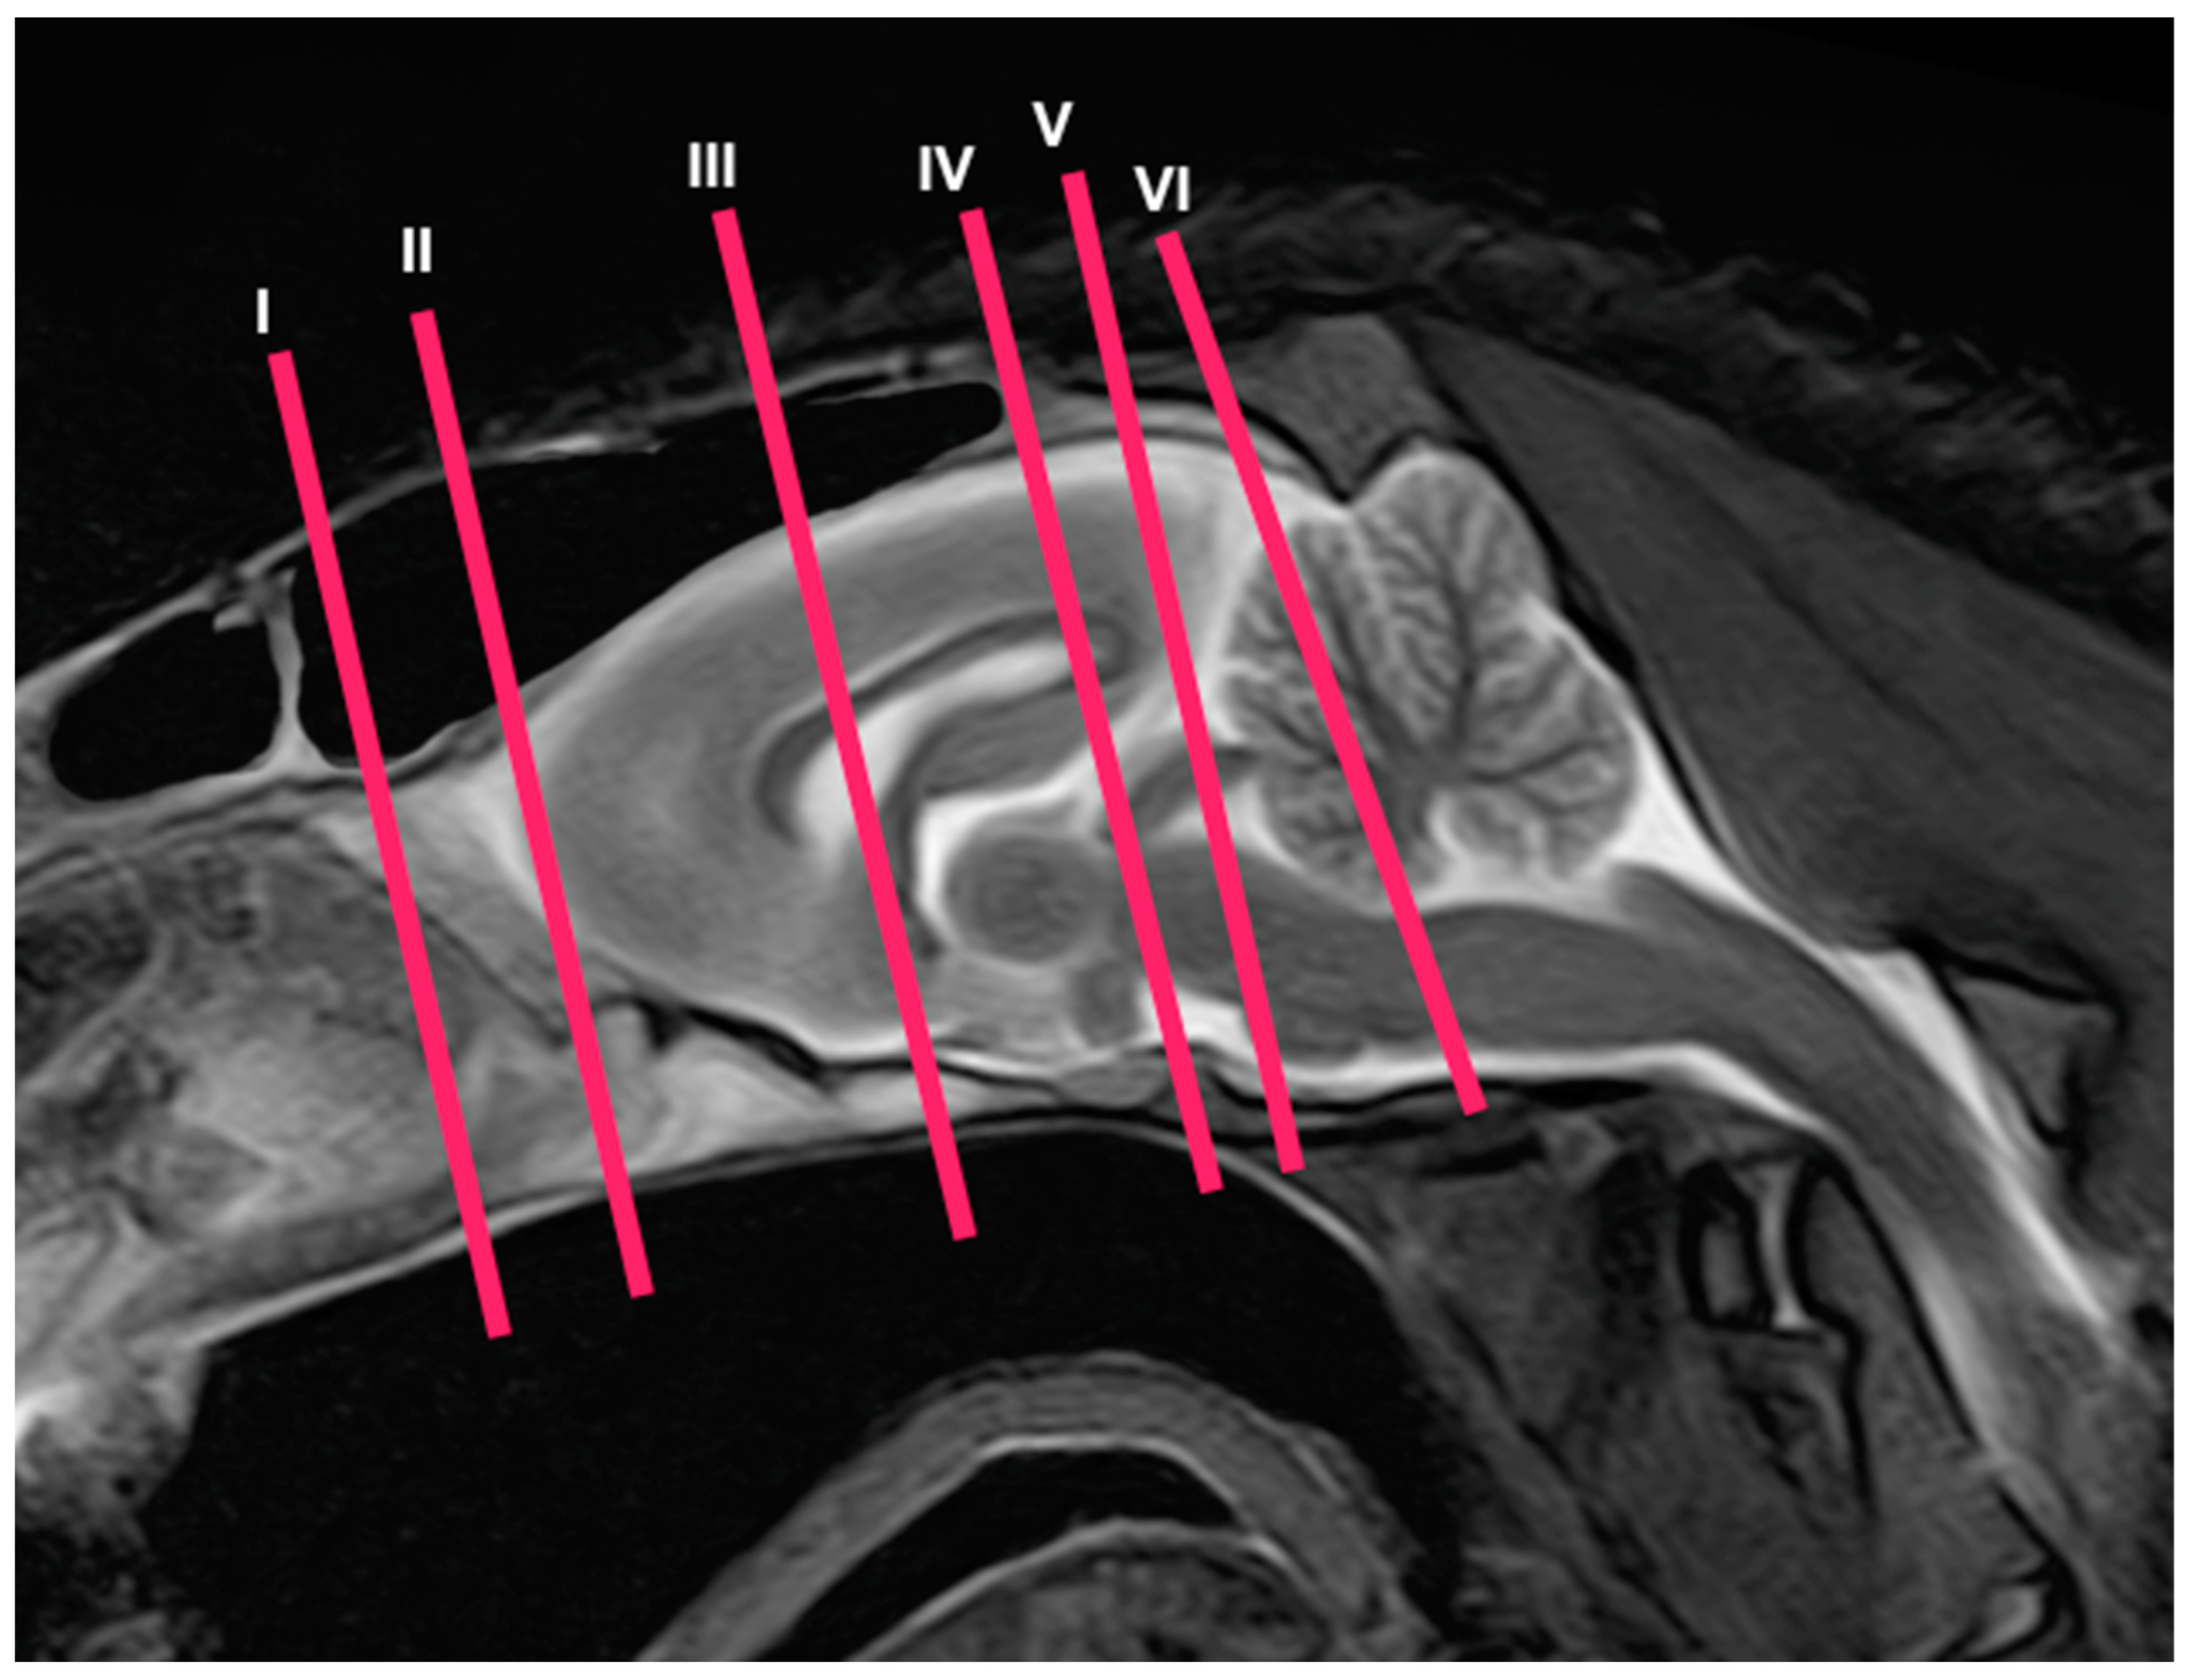

3.2. Magnetic Resonance Imaging (MRI)